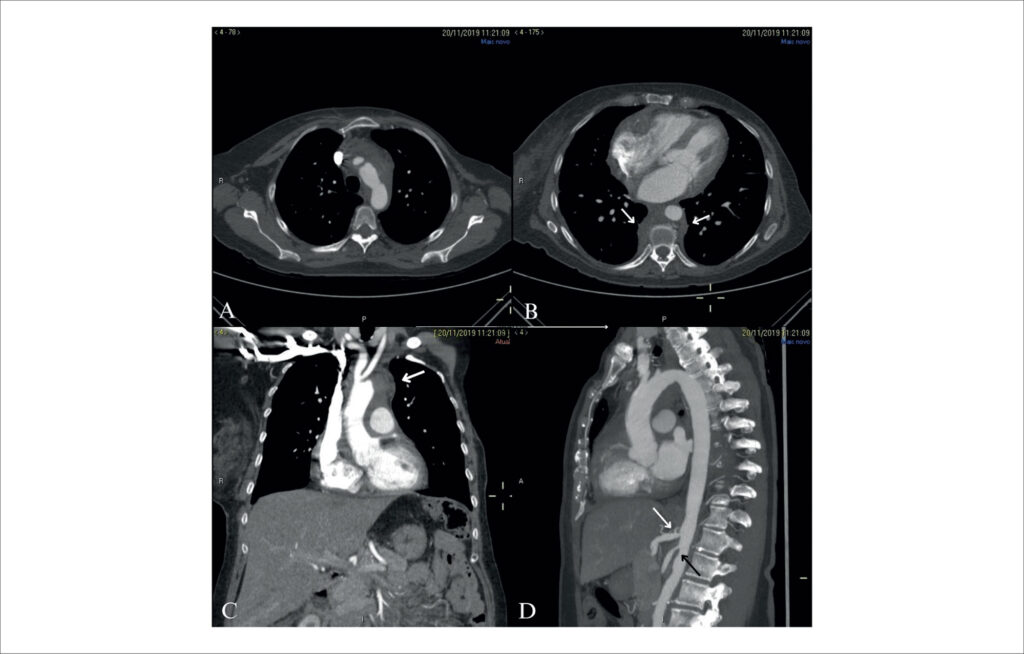

Tamponamento Cardíaco: Apresentação Clínica Inicial de Mediastinite Fibrosante

A mediastinite fibrosante (MF) é uma condição rara caracterizada pela proliferação de tecido fibrótico no mediastino, apresentando-se como uma massa concentrada ou infiltração difusa., As condições clínicas podem variar de benignidade a obstrução de estruturas mediastinais vitais, como vasos, vias aéreas e o esôfago. As queixas comuns são tosse, dispneia, infecção pulmonar recorrente, hemoptise e dor pleurítica. O envolvimento pericárdico não é relatado com frequência na literatura. Neste relato, descrevemos um caso raro de derrame pericárdico importante com tamponamento cardíaco como apresentação inicial de MF em uma paciente com câncer.